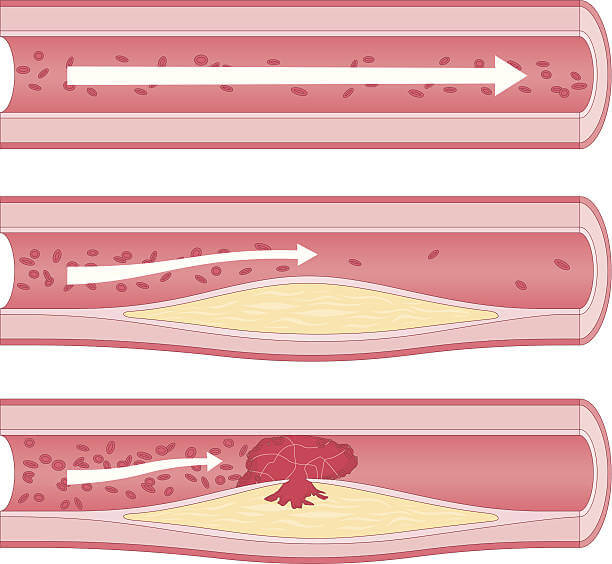

플라크 형성

플라크가 점차 성장하면서 혈관 내부를 좁혀나갑니다. 이로 인해 혈액 흐름이 제한되고 심장에 산소와 영양분을 공급하는 관상동맥의 혈류가 감소합니다.

혈전 형성

플라크의 표면이 파열되면 혈소판이 그 곳에 집착하여 혈전(응고체)이 형성될 수 있습니다. 혈전은 동맥을 완전히 막을 수 있어 심장에 심각한 손상을 초래할 수 있습니다. 이렇게 동맥 경화증이 진행되면 관상동맥의 혈류가 감소하고, 심장 근육에 충분한 혈류가 공급되지 못하면서 협심증이 발생합니다.